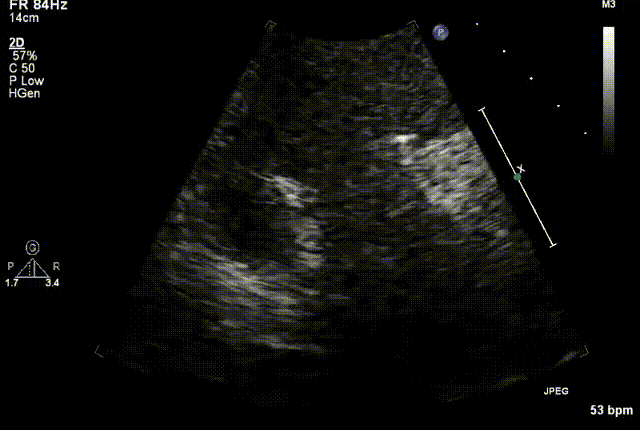

复查心超图

在本次救治性临床研究中,治疗的两例患者病因不同解剖结构复杂,均为极重度三尖瓣反流,手术最终都顺利植入了LuX-Valve Plus三尖瓣人工瓣膜。术后超声显示瓣膜支架固定稳定,反流症状显著改善,取得了良好临床治疗效果。